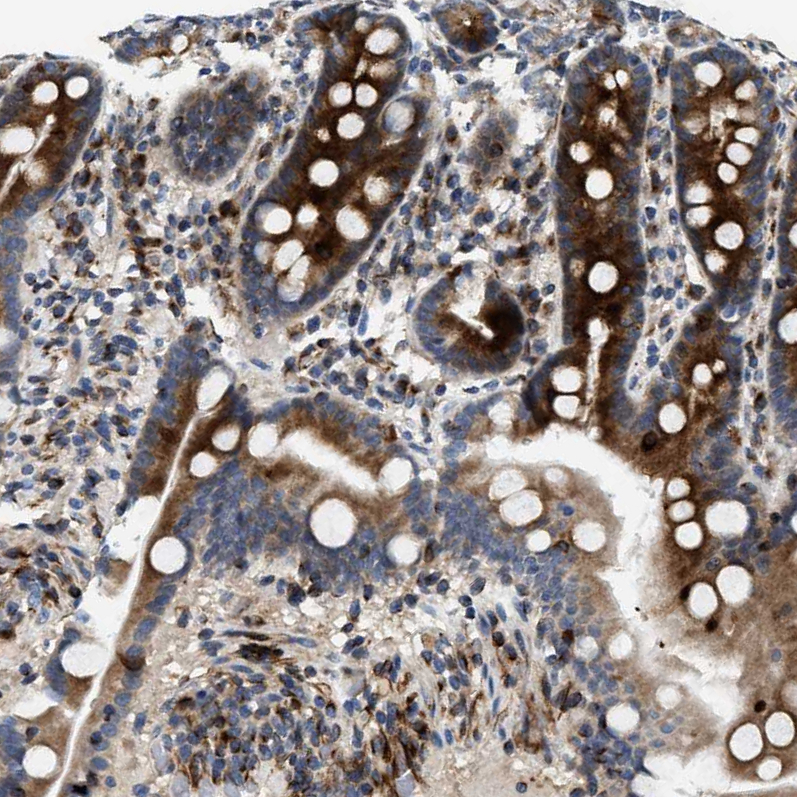

Immunohistochemical staining of human prostate shows moderate cytoplasmic positivity in smooth muscle cells.